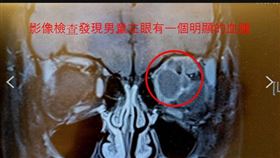

傷勢曝!新兵打靶意外…沒眼珠、碎片卡腦

機步234旅18歲邵姓義務役男昨天(22日)下午在成...